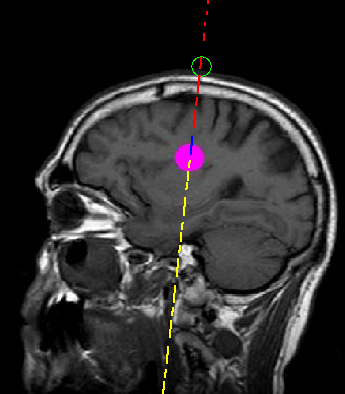

In-Plane Annotation

This annotation type is used when alpha is between 0 and 60 degrees.

A circle and a dashed line appear on the screen, as follows:

• The circle appears at the needle-tip location.

• The dashed line marks the projected path of the needle.

• A red dashed line represents the path before the slice.

• A yellow dashed line represents the path after the slice.

• A blue dashed line represents the path inside the slice.

An example of this kind of annotation is shown in figure 3.

Fig. 3 | In-Plane Annotation.